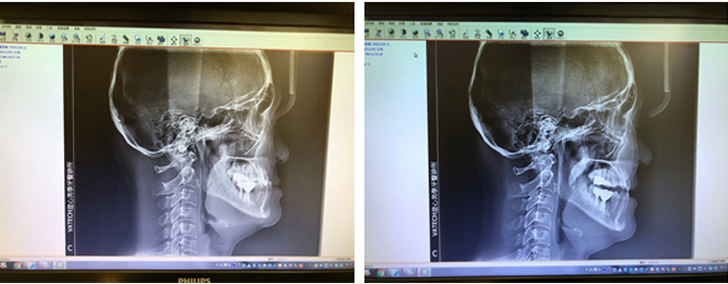

在正常咬合中,上顎所有牙齒應該覆蓋在下顎牙齒的外側,門牙也是,如果有相反的咬合,就是下顎牙在上顎的外面,就稱為錯咬。所以,若下顎門牙咬在上顎門牙的外側,也就是所謂的「前牙錯咬」,這是屬於牙齒的部分。若在側頭顱分析上,也呈現下顎骨在上顎骨的標準夾角 3度以下,甚或相反跑到上顎骨的前方,那在分類上就是屬於有骨性戽斗了,而非單純的牙齒錯咬問題。

真的戽斗:牙齒咬合情況完全由骨頭位置造成,無咬合干擾,下顎無法在閉合時後退到碰到上顎前牙切端。

假性戽斗:病患呈現出來的牙齒咬合,不完全由骨頭位置造成,同時伴有牙齒功能性干擾,此時,雖然咬起來時,一樣下顎前牙咬在上顎前方,但當放鬆時輕輕閉闔起來,下顎位置是可以後退,下顎前牙是可以碰到上顎前牙切端的,此時上下切端碰到的咬合位置才是病患真正的骨骼位置,常常這時側臉的外觀就沒有那麼戽斗了。

如果屬於這樣的假性戽斗咬合,單純用牙齒矯正來治療時,較常可以獲得良好的改善。